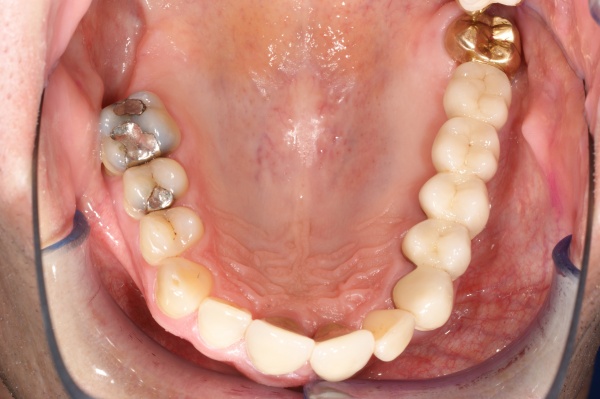

Ab dem Februar 2004 wurde der Patient zur Sicherung des Behandlungserfolges in das in der FU VIIa – Zahnmedizin seit 1996 praktizierte Recallsystem aufgenommen. Diese Erhaltungstherapie beinhaltet die bereits erwähnten Maßnahmen der Unterstützenden Parodontitistherapie (UPT). Aufgrund dienstlicher Erfordernisse (u. a. immer wieder Seefahrten des Patienten) konnte der zunächst geplante Abstand von vier Monaten nicht immer eingehalten werden. Ein Abstand von ca. sechs Monaten konnte jedoch trotz der teilweise schwierigen Rahmenbedingungen realisiert werden. Am Zahn 44 kam es im Jahr 2006 zu einem Rezidiv, sodass an diesem Zahn im September 2006 eine Lappenoperation durchgeführt wurde. Der intraoperativ vorgefundene tiefe cirkuläre vertikale Defekt führte zur Einschätzung einer langfristig fraglichen Prognose von 44. Im Zuge der weiteren Erhaltungstherapie zeigten sich bis auf 44 die parodontalen und periimplantären Gewebe völlig unauffällig: So betrugen die Sondiertiefen bei entzündungsfreien klinischen Verhältnissen durchweg zwei bis drei Millimeter. Auch radiologisch zeigten sich keine Auffälligkeiten. Es gab keine Progredienz der ehemaligen parodontalen Erkrankung, die Osseointegration der Implantate zeigte keine Veränderungen (s. Abb. 7). Erhöhte Sondiertiefen verblieben lediglich am Zahn 44. Nachdem sich trotz regelmäßiger Nachsorge an 44 keine Entzündungsfreiheit der marginalen Gingiva erzielen ließ und die Zahnlockerung von 44 zunehmend stärker wurde, erfolgte im Jahre 2010 die Entfernung des Zahnes und der Ersatz durch eine implantatgetragene Krone (s. Abb. 8). Die Erhaltungstherapie wurde fortgeführt, Behandlungsmaßnahmen über die Inhalte der UPT hinaus waren bis zur Entlassung des Soldaten im Jahre 2012 nicht erforderlich. Der Patient blieb jedoch auch nach der Entlassung aus dem aktiven Dienst Patient des Hauses, sodass die Erhaltungstherapie in der FU VIIa – Zahnmedizin fortgeführt werden konnte. Im April 2013 stellte sich der Patient mit Beschwerden am Zahn 45 vor, der Zahn wies zudem eine Lockerung des Grades II auf. Die durchgeführte Röntgendiagnostik (s. Abb. 9) zeigte eine Wurzelfraktur im apikalen Wurzeldrittel, ein Zahnerhalt von 45 war nicht möglich und der Zahn wurde noch in gleicher Sitzung entfernt. Zur Versorgung der Lücke wären verschiedene prothetische Lösungen möglich gewesen. Letztlich fiel die Entscheidung zugunsten eine Extensionsbrücke von regio 45 auf 48. So konnte die Implantatkrone 44 belassen und mit dem Lückenschluss mittels einer vergleichsweise einfachen und schnellen prothetischen Versorgung auch die Schaltlücke 46 geschlossen werden. Der Patient befindet sich nach wie vor in der FU VIIa in der Erhaltungstherapie, die Fotos zeigen den aktuellen klinischen Befund in der Aufsicht des Ober- und Unterkiefers (s. Abb. 10, 11).